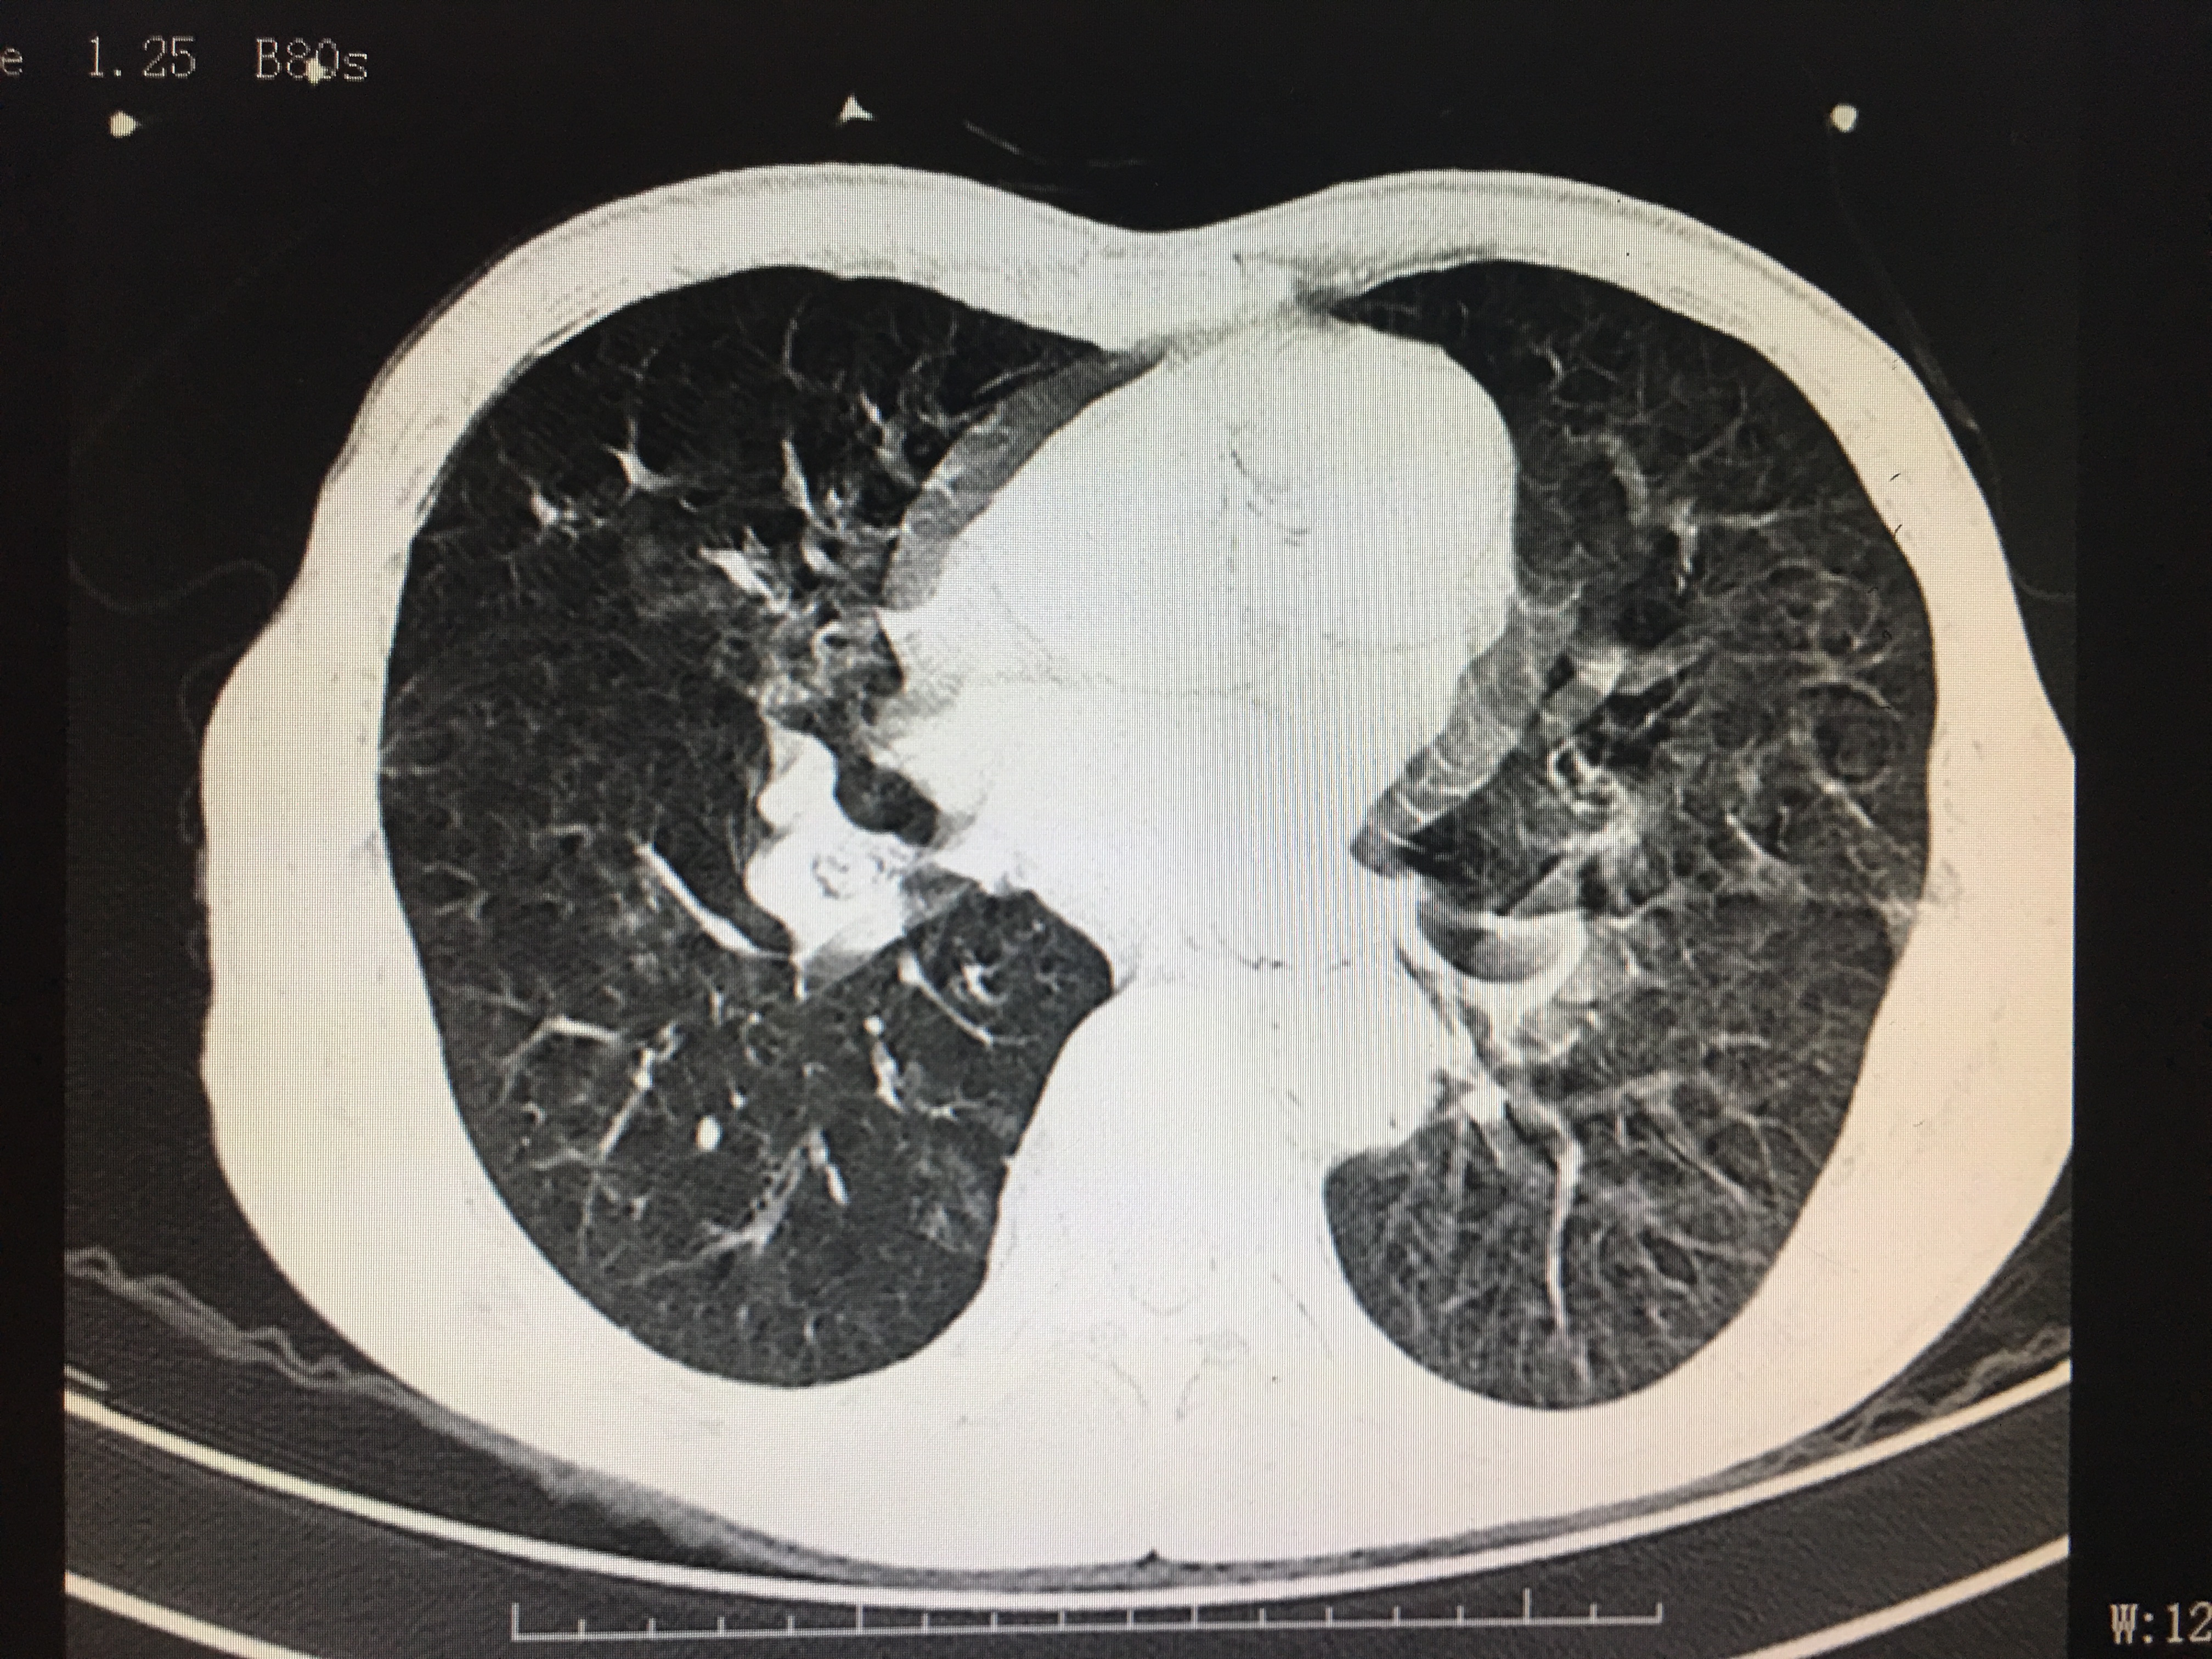

屏气没做好的图像

相信这两个图像的区别很多人都能明显的看出来,第一张图明显比第二张清晰:图2显示模糊,伪影较多,就好像手机拍照时手抖了一样,而图一清晰更容易看出是否有病变存在。如图中,图一可明显看清双肺存在散在的结节灶,而第二张图因为没屏住气,形成的伪影比较多,就算有结节灶也未必能看出来。而肺部的结节灶大部分为良性的,一般建议定期复查,部分恶性病灶进展时通过复查对比可发现。

因为采集CT图像时,是射线一瞬间穿透人体投影成像的,人的胸廓因为呼吸活动起伏,很容易影响到成像时的信息采集。所以。做过胸部CT的人不知道有没有留意到:当影像医生将要采集CT图像时,会语音提示:“吸口气-屏住呼吸-可以呼气了”。所以这一小小提示,如果做好了,能更好的让专科医生能更清晰的看到你的检查结果,有助于判断的病情,使你的检查更加有价值哦。